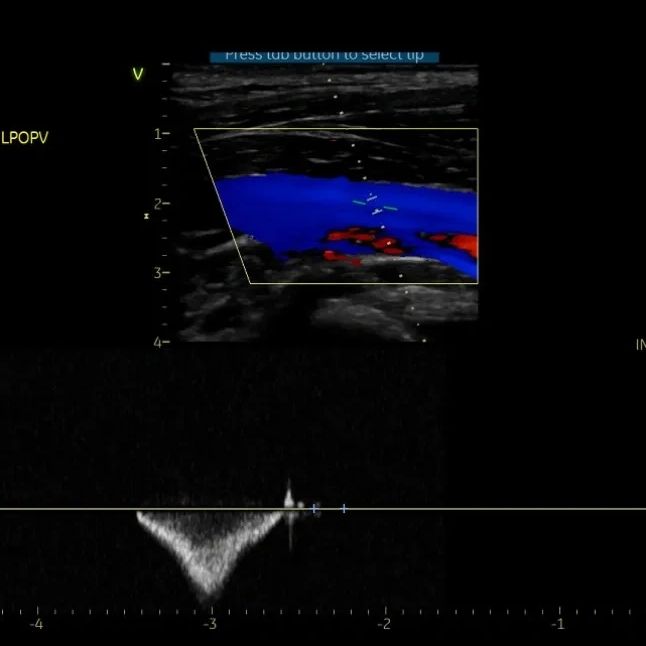

Evaluación de la circulación venosa y posibles problemas en las venas de las piernas.